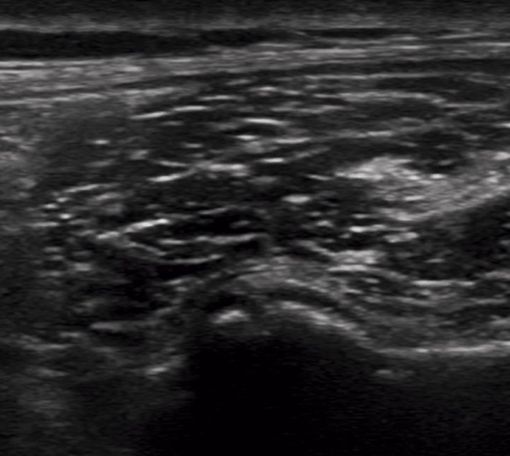

腰痛への超音波エコーガイド下鍼

腰部の筋・神経の状態をリアルタイムで確認し、原因に直接アプローチ。ぎっくり腰や慢性腰痛にも安全に施術します。